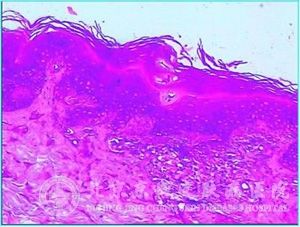

黑棘皮病的重要病理变化有哪些呢?黑棘皮病是一种生活中的常见疾病,很多都有黑棘皮病的困扰。黑棘皮病一般症状为皮肤有严重的色素沉着,影响外观,所以给患者的生活与工作等各方面都造成了很大的影响。那么对于黑棘皮病来说,黑棘皮病的重要病理变化有哪些呢?

北京京城皮肤医院指出:黑棘皮病的重要病理变化表现为 乳头向上突起,一般呈手指状,两个乳头间凹陷,表皮呈轻、中度棘层肥厚,充满角化质。乳头顶部及乳头突起侧面的表皮通常会变薄。